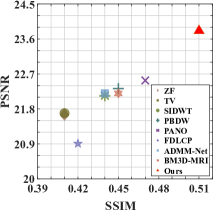

First, we test on 25 T1-weighted MRI data using three different undersampling patterns with a fixed 10% sampling rate. Fig. 3 shows the quantitative results (PSNR). Our method performances best for all three cases and has stronger stability compared with the second best method on variance. As for the effect of sampling ratios variation, we use radial mask under 10%, 30% and 50% sampling rates with evaluation of RLNE and MSE. Fig. 4 shows that our method has the lowest reconstruction error for all sampling rates. For more intuitive comparison, we illustrate the reconstruction error in term of pixels in Fig. 5. We also offer the qualitative comparison in Fig. 6. Visualized results demonstrate our method has better performance in both artifacts removing and details restoration. Time consuming is also considered. We compare our method with others on the 25 T1-weighted data using Radial mask with 10% and 50% sampling rate. Notice that ADMM-Net and ours are tested on GPU for the incorporation of deep architecture. Tab. 1 shows that our method provides an efficient reconstruction process and comes to the fastest method among the state-of-the-art competitors.